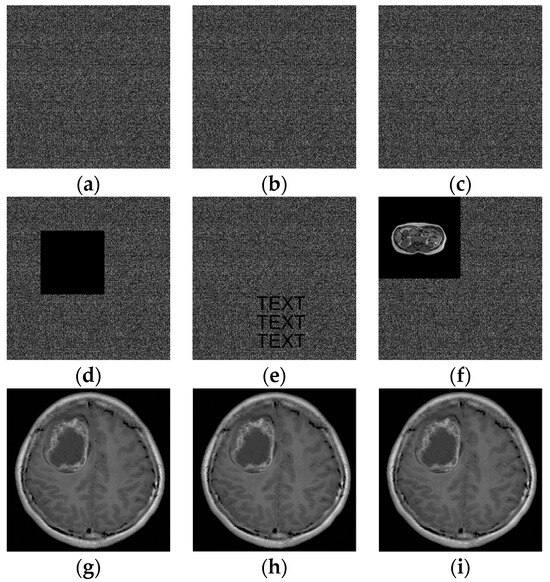

4.3. Recovery Evaluation

In order to verify the performance of the tamper recovery scheme in the proposed scheme, ShareA of Brain 01 is used as an example here, and an attack test is carried out on ShareA with embedded secret data and authentication bits. Three classic attack methods are adopted, including content cropping, text addition, and content exchange. The attack results and tampering recovery results are shown in Figure 11.

Figure 11.

Results of attack test. (a–c) ShareA; (d–f) the attacks of content cropping, text addition, and content exchange carried out on ShareA; (g–i) the recovered ShareA.

The first column shows a content cropping attack on ShareA, from which a block with a size of 200 × 200 is cropped. The second column performs a text addition attack on ShareA. The third column is replaced with “Pulmonary 01” in the upper left corner of ShareA; its size is 256 × 256, and the last line represents the recovery result of ShareA after the attack. In addition, the same attack was tested on ShareB, and the same results were obtained.